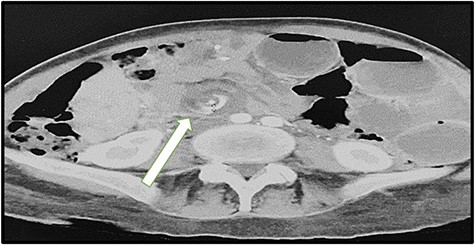

A 43-year-old lady was seen at the Surgical Accident and Emergency Department with a 14-day history of severe colicky abdominal pain, nausea and vomiting. She had a background history of LRYGB in 2011 and laparoscopic repair of internal hernia in 2017. Upon admission, her vitals were pulse (P): 86 bpm, blood pressure (BP): 120/80 mmHg and temperature (T): 37.5. The patient appeared to be malnutrition and dehydrated. Abdominal examination, mild distension, epigastric and para-umbilical tenderness and digital rectal exam (DRE) was empty. Intravenous fluids were administered and laboratory tests were sent. Full blood count (white blood count (WBC): 11.5 109 g/l, HB: 12.0 109 g/l and platelet: 373), kidney profile (creatinine: 37 and urea: 2.1) and lactic acid were high (2.28). We ordered a computed tomography (CT) scan that immediately showed dilated bowel loops with crowded engorged mesenteric vessels showing swirling sign at the paramedian plane, with fluid surrounding the intestinal loops, suggestive of high-grade small bowel obstruction due to internal hernia (Fig. 1). The radiologist compared this result with the CT findings of 2017, which showed the same mesenteric swirling of vessels with a lymph node (Fig. 2). The surgical team discussed the result with the patient, and we obtained consent for exploratory laparotomy.